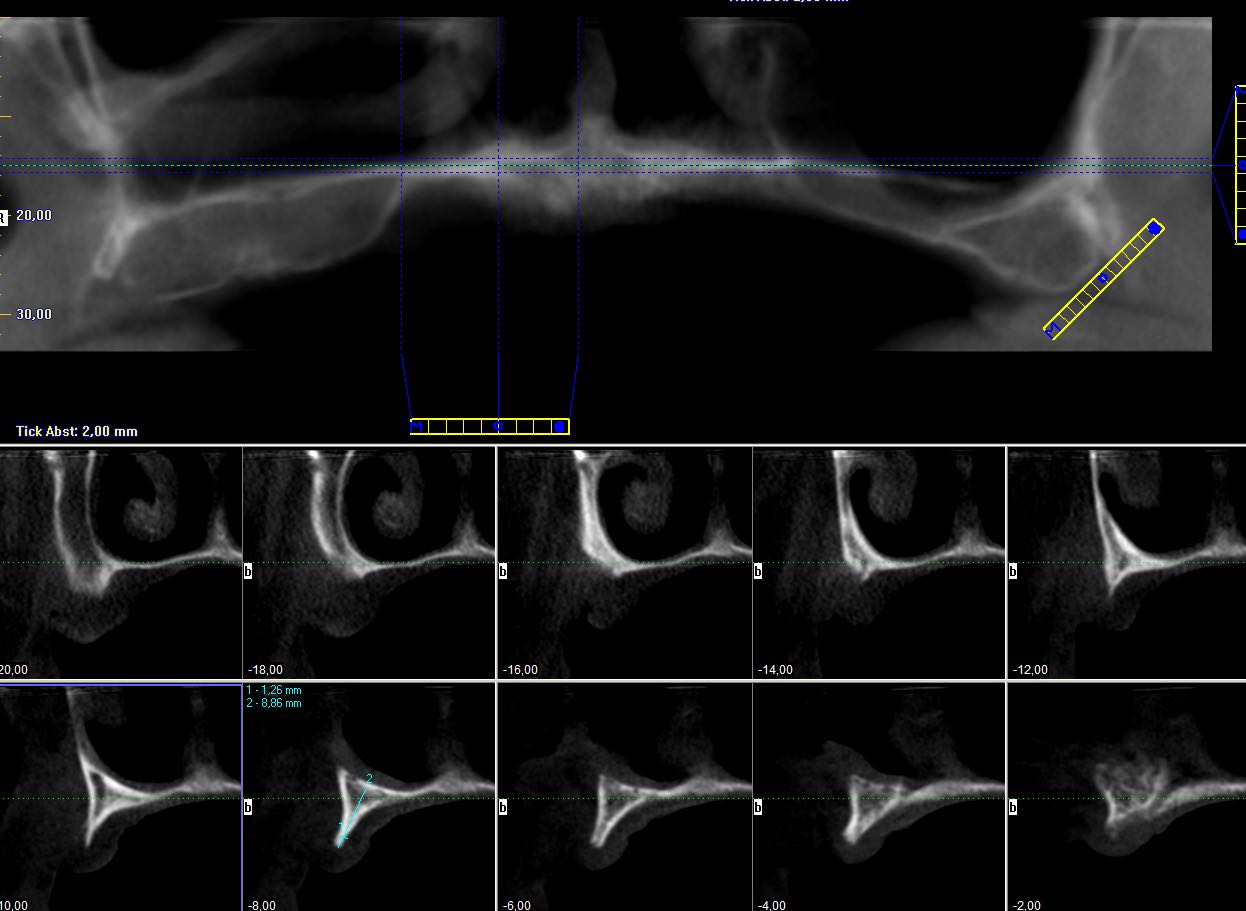

2/23 - Preoperative radiological situation – severely atrophic maxilla

Full arch reconstruction of the maxilla with maxgraft® bonebuilder - Dr. M. Erbshäuser

3/23 - Preoperative radiological situation – severely atrophic maxilla

4/23 - Preoperative radiological situation – severely atrophic maxilla